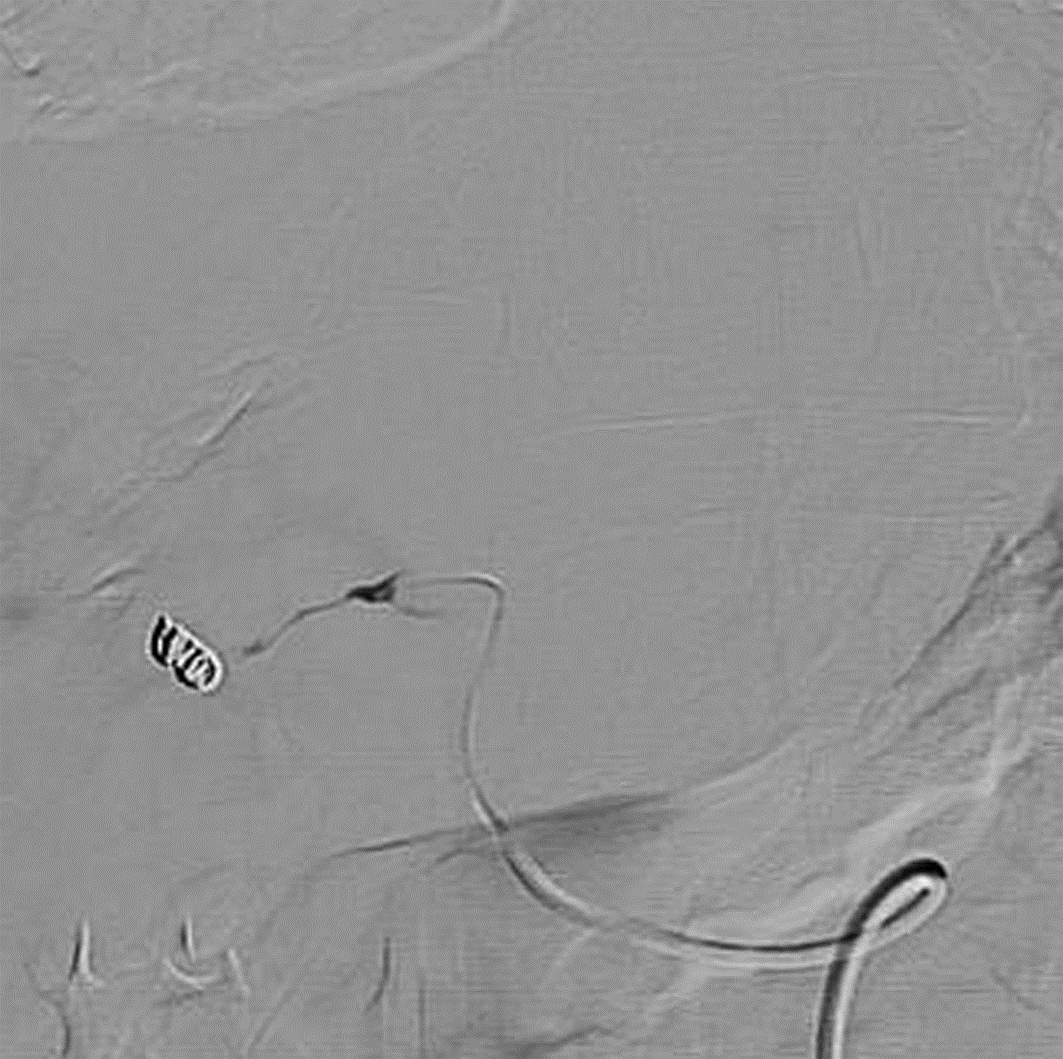

Diagnosis and treatment of hepatic pseudoaneurysm with bile leakage and bile duct hemorrhage after transplantation of donor liver with right hepatic artery variation: A case report

Tian HAN, Rui ZHANG, Zhiyong SHI, Li ZHANG, Jun XU

2022, 38(12): 2818-2820. DOI: 10.3969/j.issn.1001-5256.2022.12.024

Abstract(1727) HTML (1056) PDF (2268KB)(55)